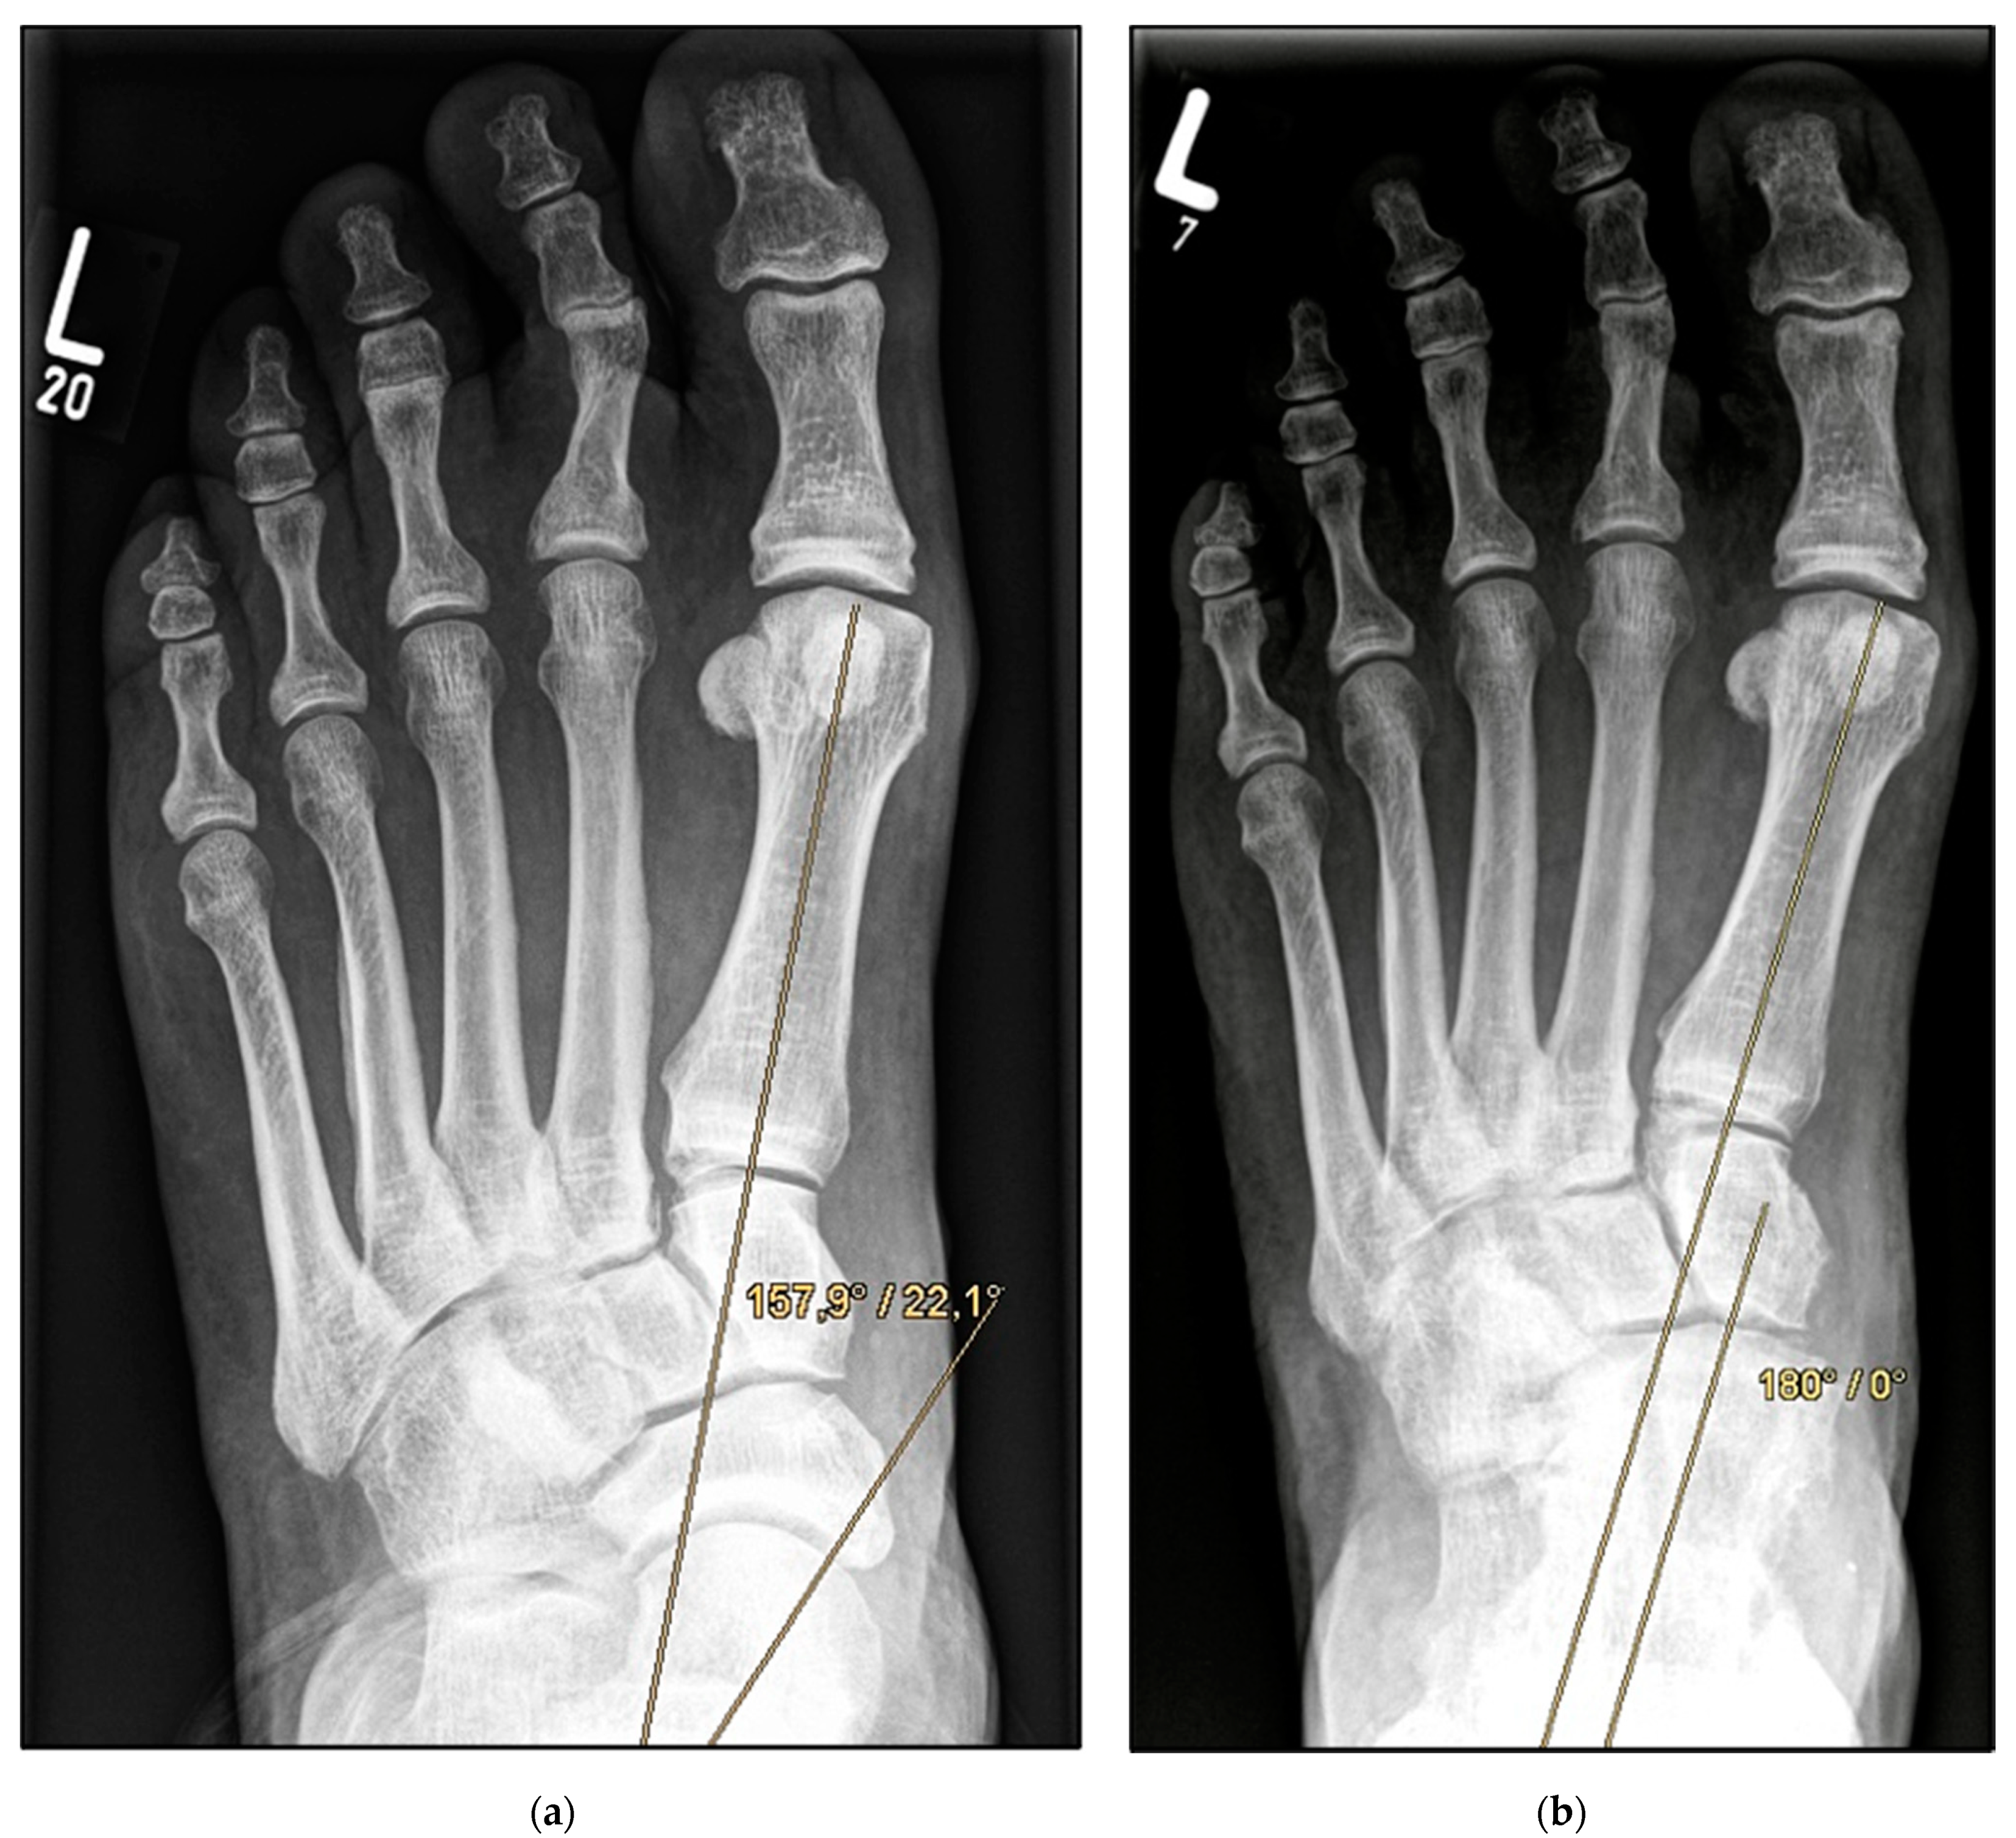

Figure 2.

Pre- and post-operative radiographic findings of combined talonavicular arthrodesis and calcaneal displacement osteotomy, left foot. (a) Anteroposterior view pre-operative, (b) anteroposterior view post-operative.

Medial calcaneal displacement osteotomy and talonavicular arthrodesis (Group A). In the first step, a V-shaped osteotomy was performed via an oblique approach to the lateral calcaneus with medial displacement of the back portion of the calcaneus. Osteotomy was performed using either an oscillating bone saw or bone chisel. Depending on the extent of the deformity, a medial displacement of approximately 8–10 mm was considered optimal. Fixation was achieved by means of two percutaneously inserted lag screws with diameters of 4.0–6.5 mm. The second step was talonavicular arthrodesis via a dorsal approach, usually with interposition of an iliac crest bone graft. Fixation was performed using two or three screws with diameters of 4 mm or a combination of screws and Nitinol compression implants (Figure 2a,b and Figure 3a,b).